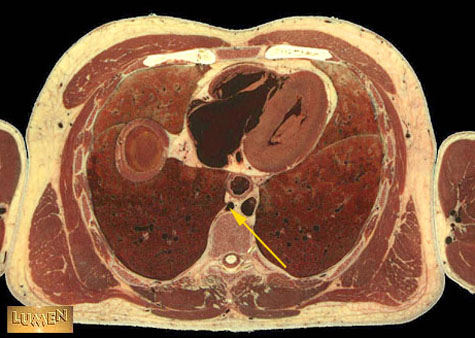

Identify.

Answer

Azygous vein.